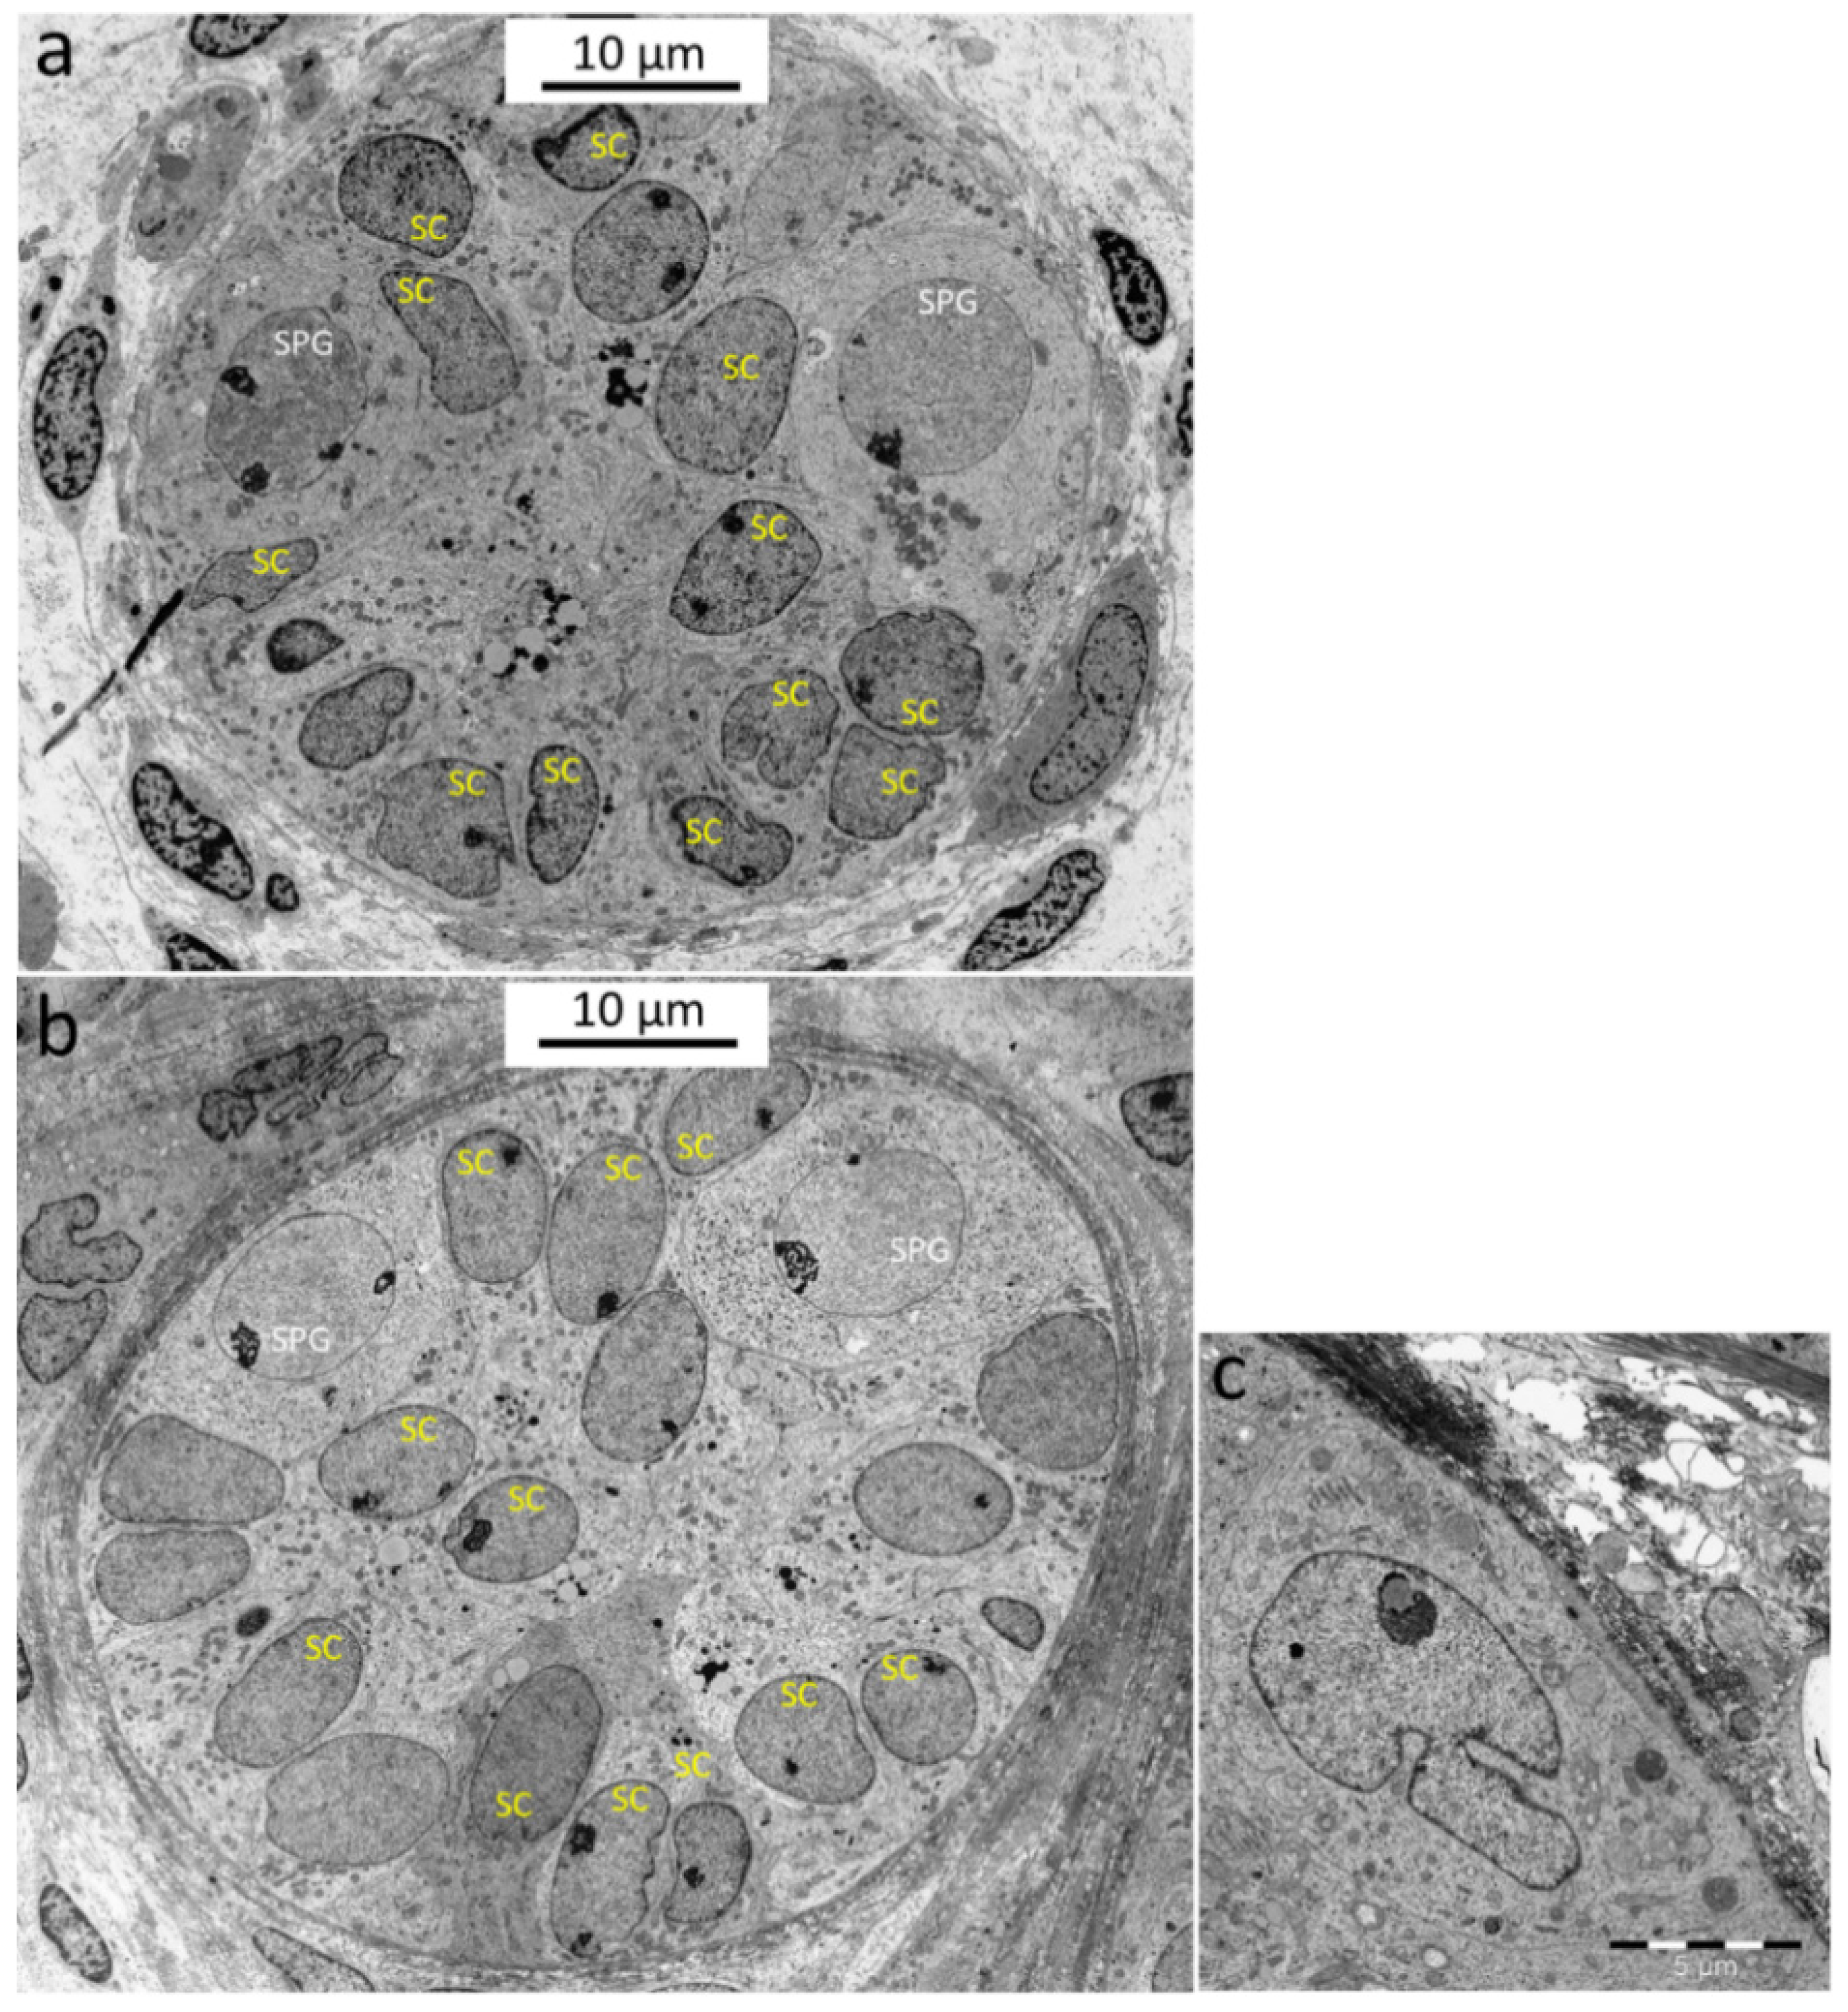

3.7. Characterization of SCs by Immunofluorescence Staining and TEM: TEM Shows SC Maturation Trends as SC Nuclei Become More Lobulated after 3 Weeks of Cultivation